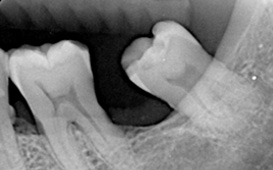

| X光檢查 | 硬組織型態 |

牙周組織破壞包括 :

骨頭吸收、牙齦發炎、牙齒動搖